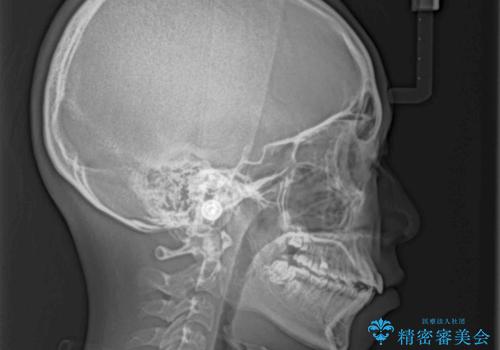

- 前歯のデコボコと八重歯を気にして来院された患者様です。

本人はあまり実感はありませんでしたが、同席されたご家族より口がすぐに開いてしまうことを指摘されていました。

口元に力の入る歯列であったため、上顎左右第一小臼歯4本を抜歯するワイヤー矯正を行うこととしました。